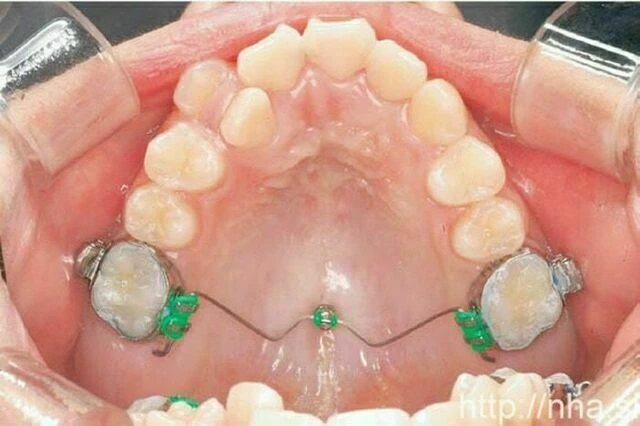

Với điều trị niềng răng mặt trong, minivis có thể được cắm giữa các chân răng ở xương ổ răng phía vòm miệng (Hình 1) hoặc vùng giữa khẩu cái (Hình 2). Ở bệnh nhân là trẻ em, đường khớp giữa khẩu cái vẫn đang mở, trong trường hợp này có thể cắm minivis ở vùng cận giữa khẩu cái (Hình 3). Trong một số trường hợp, có thể cắm minivis ở mặt ngoài ngay cả khi niềng răng mặt trong (Hình 4)

Hình 1 Minivis hàm trên cắm ở xương ổ răng phí vòm miệng.